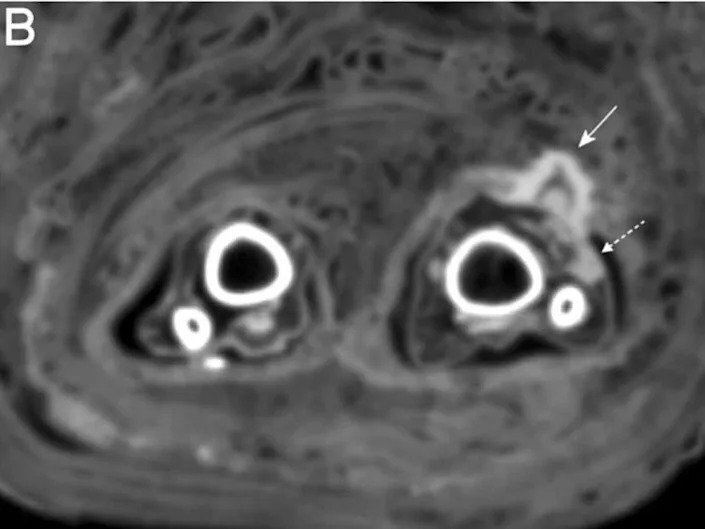

در سیتی اسکن مومیایی پانسمان زخم با «فلش پیوسته» و چرک درون زخم با «فلش مقطع» نشان داده شده است.

زینک و همکارانش هنگامی در حال انجام سیتی اسکنهای معمول بر روی مومیاییها بودند، این پانسمان را کشف کردند. سیتی اسکن نشانههایی از وجود چرک را هم در زخم نشان میداد.